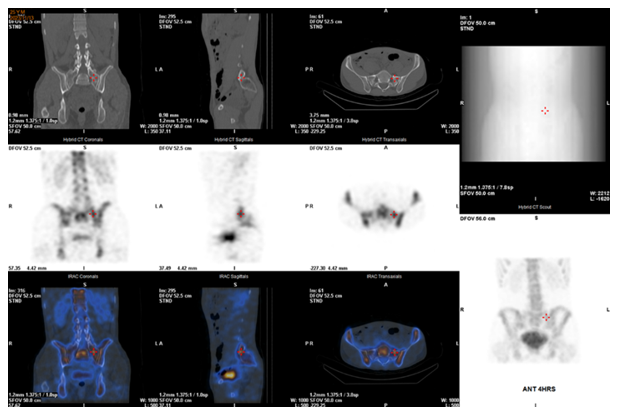

Single-photon emission computed tomography (SPECT) is a nuclear medicine imaging modality employed for the functional assessment of tissues and organs, distinguishing itself from purely anatomical imaging techniques.4 Furthermore, integrating images of SPECT and computed tomography (CT) provides explicit sites due to CT’s morphological characterization and more accurate localization from SPECT at the uptake site.5 To our amazement, SPECT can also play a crucial role not only in radiation treatment planning but also in the evaluation of therapy response.6 SPECT-CT was also employed to precisely identify the specific location and target the lesion for accurate therapeutic intervention in our case. We present a case with remarkably intense uptake in the pseudo-joint observed through scintigraphic imaging, demonstrating complete remission of pain following interventional steroid injections.

Notably, SPECT revealed an exceptionally intense uptake in the left pseudo-joint, indicating the potential location of the severe pain (Figure 2). Eventually, after obtaining his agreement, significant efficacy was observed following steroid injection of the pseudo-joint. He did not visit our clinic in the subsequent two year.

Figure 2 Remarkably intense uptake in the left pseudo-joint of transitional vertebra, indicating the location of severe pain of the patient.

We present a case of fitful and recurring lower back tenderness. Concurrently, X-ray revealed a typical transitional vertebra in the lumbosacral junction. Furthermore, SPECT-CT effectively showed intense uptake in the left pseudo-joint of this LSTV, indicating the location of the severe pain of the patient. Steroid injection was administered promptly and demonstrated significant therapeutic efficacy.

SPECT-CT distinguishes itself from purely anatomical imaging modalities by producing a 3-dimensional image of the distribution of a radioactive tracer.4 Additionally, degenerative diseases and neoplastic processes, especially inflammation in the musculoskeletal region, were all precisely detected by SPECT-CT.8,9 One case report even revealed that the pain improvement of surgical fusion was due to the successful evaluation of increased osteoblastic activity with anatomic precision by SPECT-CT.10 In our case, we implemented the identical methodology, achieving precise localization at the pseudo-joint. By administering steroid injections directly at the lesion, we achieved remarkable therapeutic outcomes. Given its efficacy in pain management, this procedure merits widespread adoption.